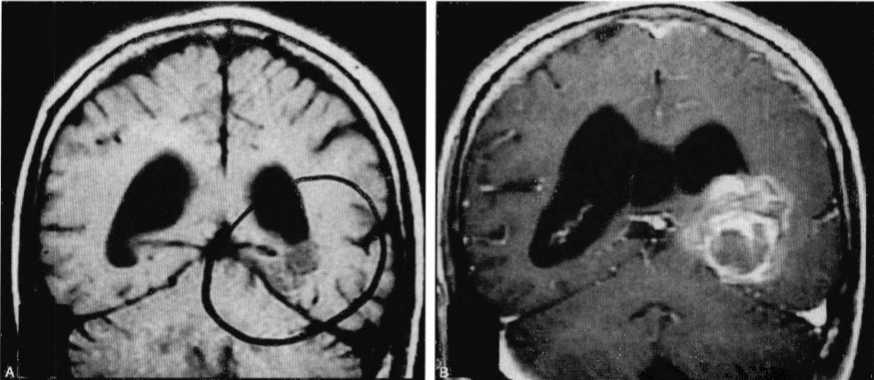

圖1:此患者一直以來(lái)隨訪(fǎng)一個(gè)左側(cè)題枕內(nèi)側(cè)的海綿狀血管瘤。有頭痛但無(wú)其他不同癥狀。(A)原來(lái)的MRI掃描發(fā)現(xiàn)一個(gè)2cm大小的病灶,無(wú)新近出血的證據(jù)。(B)在隨訪(fǎng)中,病灶內(nèi)出血增大。釓增強(qiáng)冠狀位MR掃描發(fā)現(xiàn)一在顳枕內(nèi)側(cè)面一有分割的出血性病灶,在側(cè)腦室體部的下方,伴有腦積水。此患者予以行腦室-腹腔分流及通過(guò)顳下溝行病灶切除